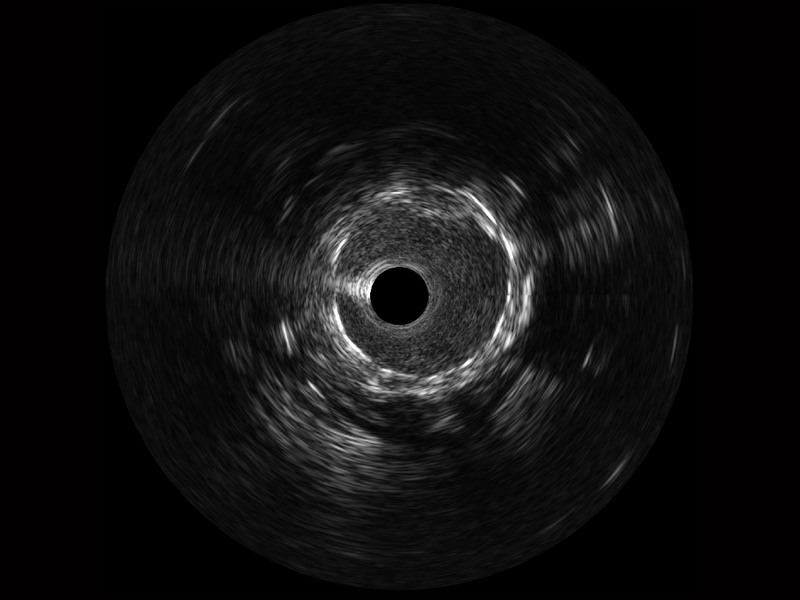

环球UG官网宽频IVUS图像

传统IVUS图像

对比传统IVUS导管成像,环球UG官网宽频IVUS图像的近场支架梁显影更细腻,远场中膜外血管仍清晰可辨,兼顾远中近,兼顾分辨力与穿透深度